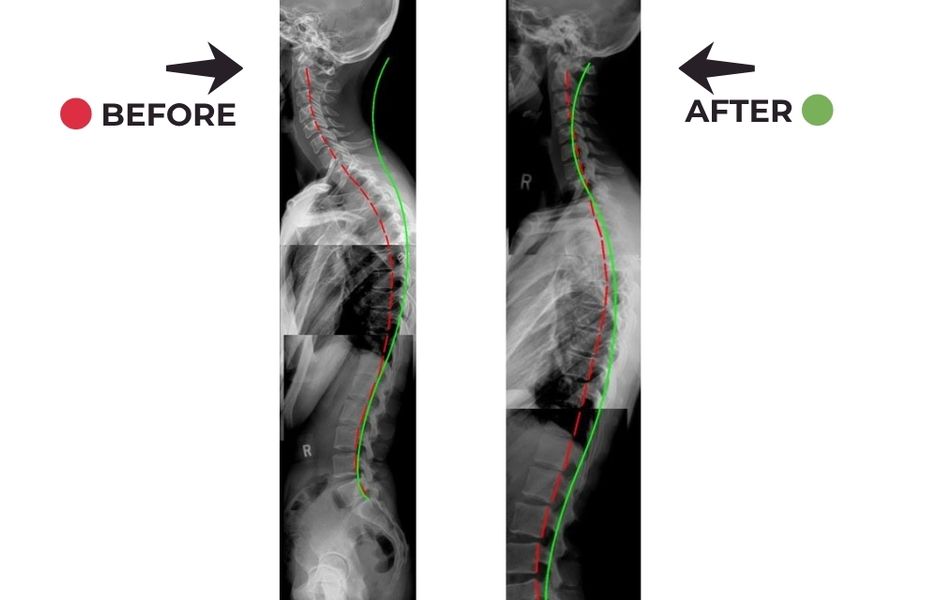

"This is the best chiropractic office by far. They provide individualized adjustments, decompression, traction, and exercises at every appointment. They do x rays regularly to diagnose and measure objectively and give individualized care. They focus on not just short term relief but the posture rehab necessary for long term results.

In many cases, yes. X-rays help us see the structure of your spine and identify underlying issues that may not be visible through a basic exam. This allows for more precise and effective chiropractic care.